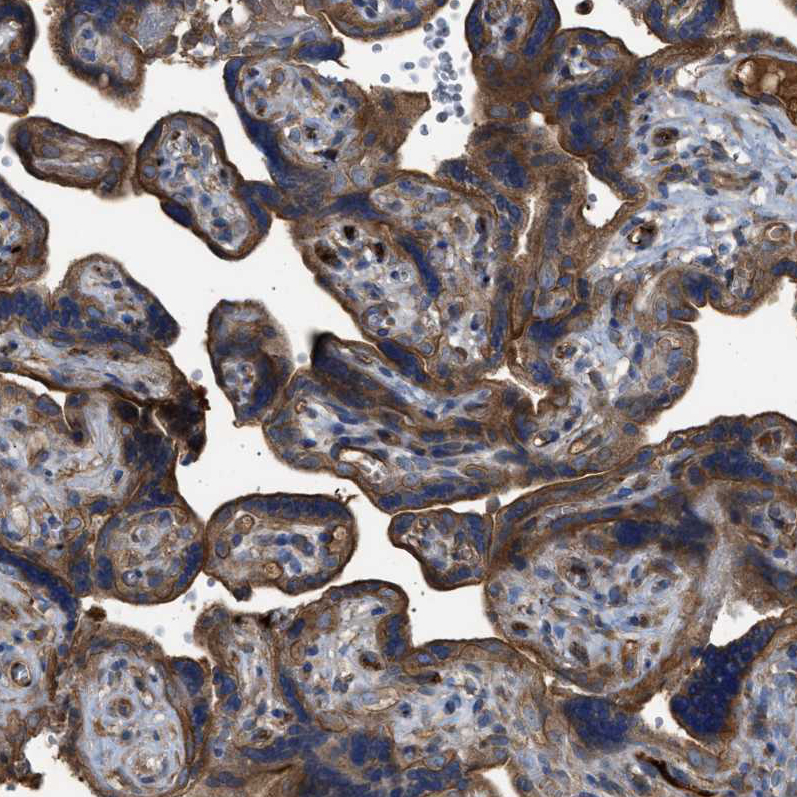

Immunohistochemical staining of human placenta shows strong cytoplasmic positivity in trophoblastic cells.